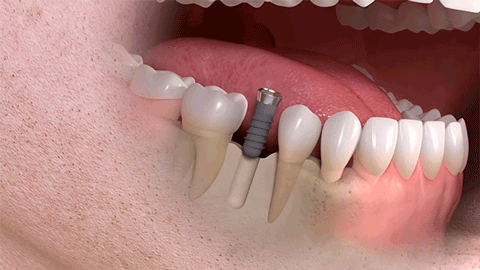

种植牙是医学界公认的理想修复方式,被誉为“人类的第三副牙”。相比活动假牙不舒服、难清洗、容易引起口腔黏膜病变,种植牙更稳固耐用,舒适美观,咀嚼功能好,一次种植,长期受用。种植牙不仅是中老年人的专利,年轻人因意外、牙病等造成的单颗、多颗牙齿缺失,也能够通过种植牙进行修复治疗,重获完美口福。

△单颗种植示例